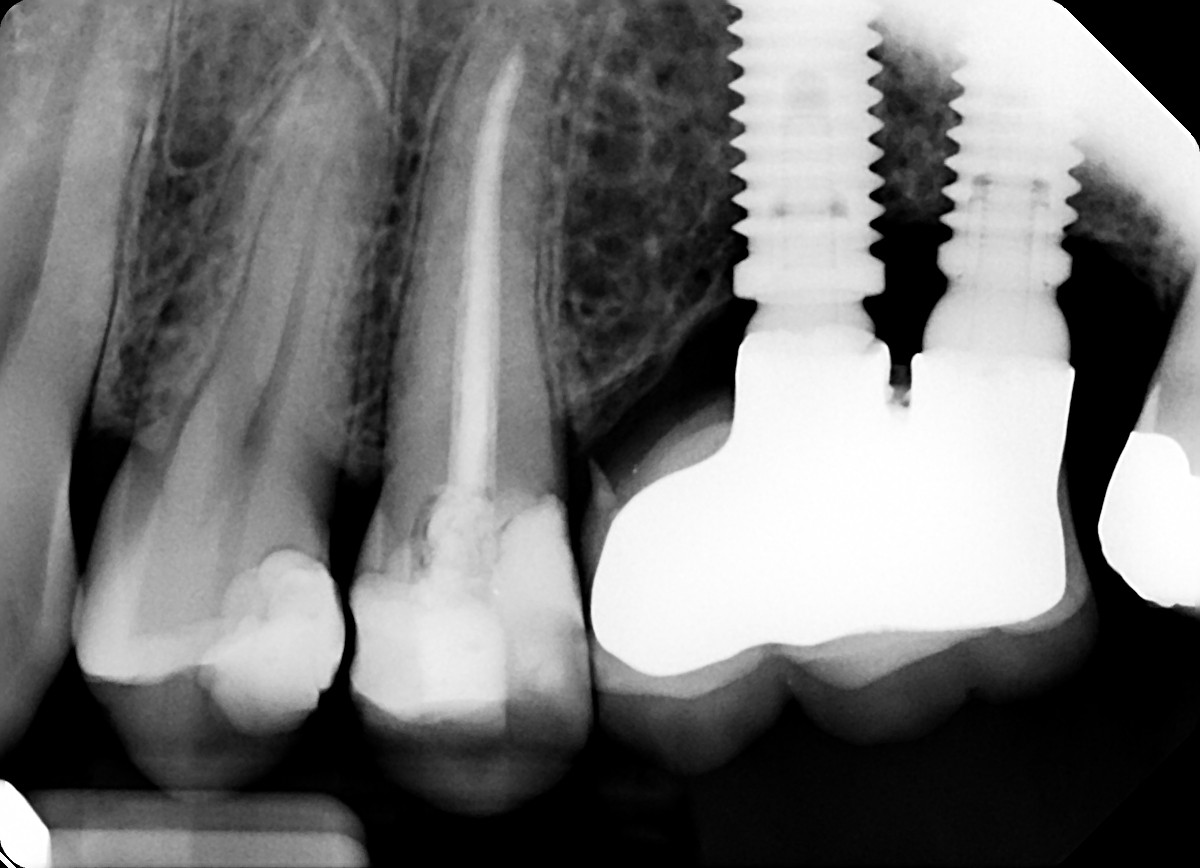

3. What option can explain the crown of the tooth #3.6?